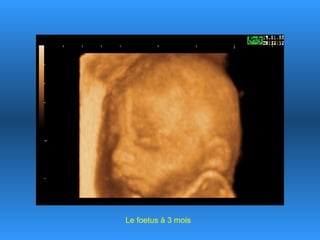

Le document traite des progrès scientifiques réalisés dans le domaine des échographies 3D. Il montre l'évolution des images du fœtus à différentes étapes gestationnelles, illustrant la clarté des images obtenues au fil du temps. Cette avancée technologique est présentée comme impressionnante, notamment pour le fœtus de 18 ans.